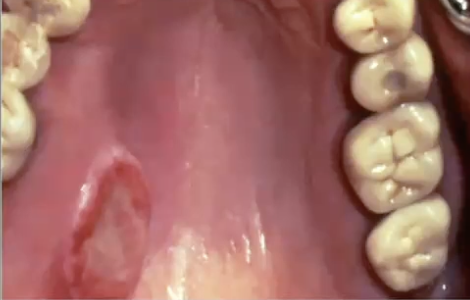

<p>What is this?</p>

What is this?

Pleomorphic adenoma in the palate